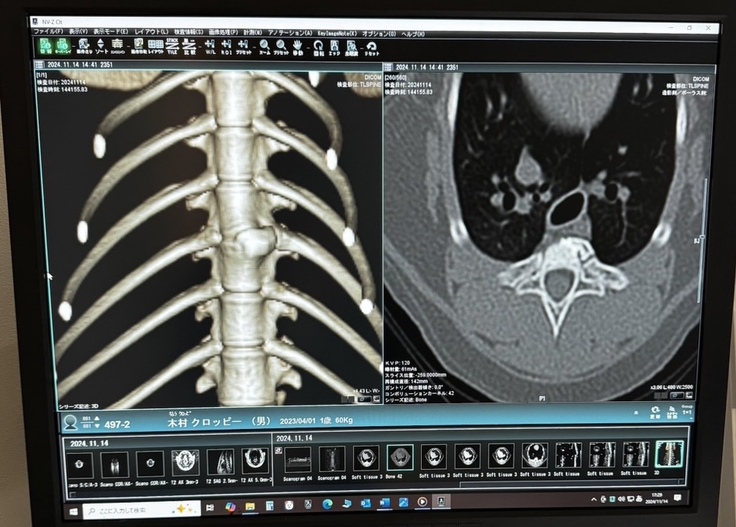

先日、MRI検査をしたクロッピー!

検査結果は後日になりますが、クロッピー、MRI検査頑張りました。

骨に異常があるかもとのことでしたが、検査結果がでたら治療を進めていきます。